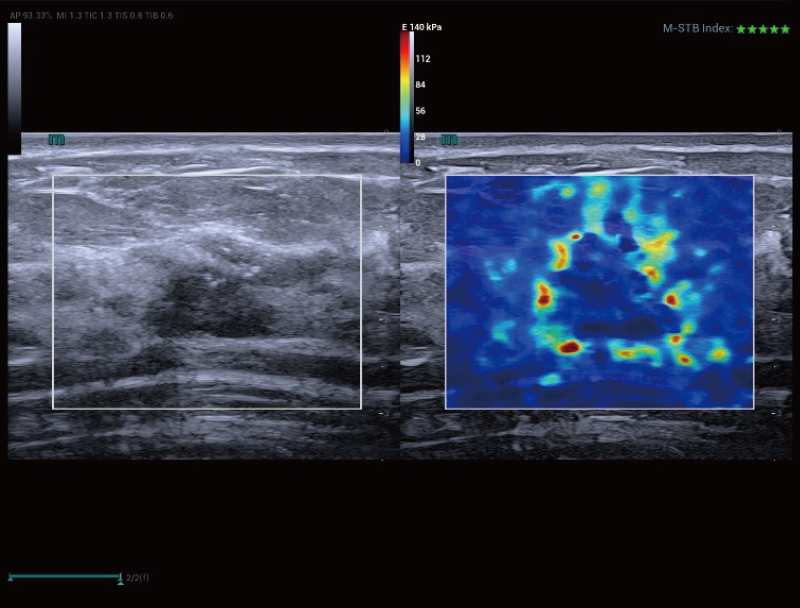

changes in lesions. Additionally, STVi shear wave viscoelastography, a

novel technique for assessing tissue viscosity, demonstrates great

potential for studies on chronic liver diseases and tumors.

STVi enables the quantitative evaluation of tissue viscosity and

provides real-time multi-parameter imaging, offering a more

comprehensive approach to imaging diagnosis and quantitative

analysis of chronic liver diseases, breast lesions, and other

conditions.

Dual quantitative coefficients

Chronic liver disease assessment

Multiple quantification tools

Breast tumor assessment